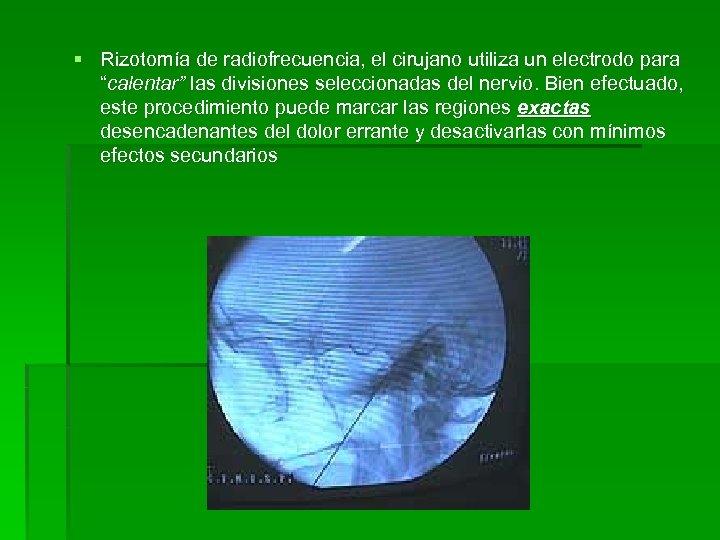

§ Rizotomía de radiofrecuencia, el cirujano utiliza un electrodo para “calentar” las divisiones seleccionadas del nervio. Bien efectuado, este procedimiento puede marcar las regiones exactas desencadenantes del dolor errante y desactivarlas con mínimos efectos secundarios

§ Rizotomía de radiofrecuencia, el cirujano utiliza un electrodo para “calentar” las divisiones seleccionadas del nervio. Bien efectuado, este procedimiento puede marcar las regiones exactas desencadenantes del dolor errante y desactivarlas con mínimos efectos secundarios

Se lleva a cabo bajo anestesia local con sedación, ya que es fundamental la colaboración del paciente. Se inserta una aguja en un punto 2. 5 -3 cm lateral a la comisura bucal. Evitando penetrar la mucosa oral, se dirige la aguja, bajo control radiológico, hacia el agujero oval de la base del cráneo. Una vez que se penetra dicho agujero, se retira el estilete. A continuación se introduce el electrodo por la aguja. Entonces el paciente es despertado de la sedación y se procede a la estimulación hasta conseguir reproducir la distribución del dolor en la cara. Entonces se seda de nuevo al paciente para realizar varias veces una coagulación parcial del ganglio trigeminal con temperatura a 65 -75 ºC.

Se lleva a cabo bajo anestesia local con sedación, ya que es fundamental la colaboración del paciente. Se inserta una aguja en un punto 2. 5 -3 cm lateral a la comisura bucal. Evitando penetrar la mucosa oral, se dirige la aguja, bajo control radiológico, hacia el agujero oval de la base del cráneo. Una vez que se penetra dicho agujero, se retira el estilete. A continuación se introduce el electrodo por la aguja. Entonces el paciente es despertado de la sedación y se procede a la estimulación hasta conseguir reproducir la distribución del dolor en la cara. Entonces se seda de nuevo al paciente para realizar varias veces una coagulación parcial del ganglio trigeminal con temperatura a 65 -75 ºC.